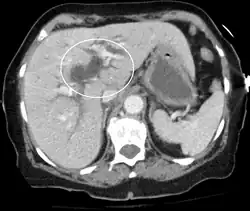

Biliary-tract dilation due to obstruction as seen on CT scan (axial plane)

Most people presenting with jaundice have various predictable patterns of liver panel abnormalities, though significant variation does exist. The typical liver panel includes blood levels of enzymes found primarily from the liver, such as the aminotransferases (ALT, AST), and alkaline phosphatase (ALP); bilirubin (which causes the jaundice); and protein levels, specifically, total protein and albumin. Other primary lab tests for liver function include gamma glutamyl transpeptidase (GGT) and prothrombin time (PT).[37] No single test can differentiate between various classifications of jaundice. A combination of liver function tests and other physical examination findings is essential to arrive at a diagnosis.[38]

Medical imaging such as ultrasound, CT scan, and HIDA scan are useful for detecting bile-duct blockage.[41]